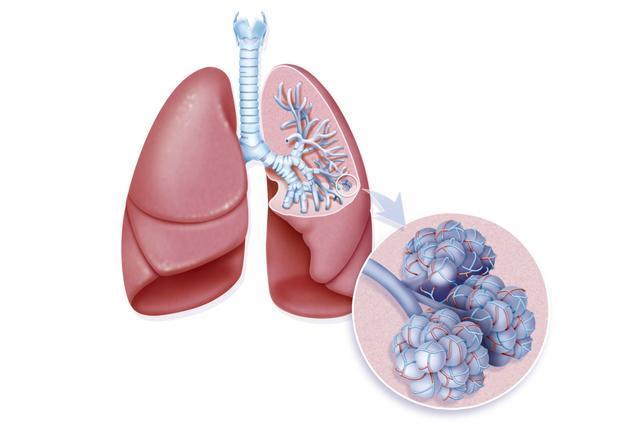

肺结节的处理如果属于结节,后期进一步检查的的重点是评估这个结节发生恶性转化的概率。这些肺结节的患者当中,对于有吸烟史、年龄超过35岁、病灶直径大于2cm,没有钙化,伴有胸部症状,或者对比原先的肺部影像学表现,发现病灶增大的人,是需要做手术切除的。那么,对于没有达到手术切除的指征的这部分人,应该做什么,以让自己更放心一些呢?>第一步:常规检查>常规进行胸部CT扫描,再对比原来的检查结果,看是否能够发现一些新的结节。这其中,有些人有钙化的表现,或者近两年内没有什么变化的,一般来说是无需进一步检查的。>第二步:可能是肺癌的,需要进一步检查>需要详细的询问病史、家族史、吸烟史,以及做一些相关肿瘤标志物的检查;如果这些检查都没有问题,说明肺癌的可能性比较小。对这一部分的患者,建议每隔3、6、12、24个月进行一次高分辨率的胸部CT检查。

>第三步:有症状患者的处理>对于有一些肺癌临床症状、长期吸烟史,或其他肺癌风险因素的人,如果觉得肺癌的可能性超过10?0?则需要进一步的做确诊检查。结节直径超过1cm的,完善PET-CT检查。如果有必要,也可以考虑做增强CT检查。周围型的结节,位置比较表浅的,可以考虑做胸壁细针穿刺吸取活检。有支气管空泡症(指肿块内有1~3mm,或说1~2mm的低密度区,是早期周围型肺癌的重要征象)的人,可以完善支气管镜检查,在支气管灌洗液中找肿瘤细胞。如果以上这些检查有问题,需要做进一步的胸腔镜手术、纵隔淋巴结检查,并送冰冻组织学检查,如证实为恶性,则进行肺叶切除手术。